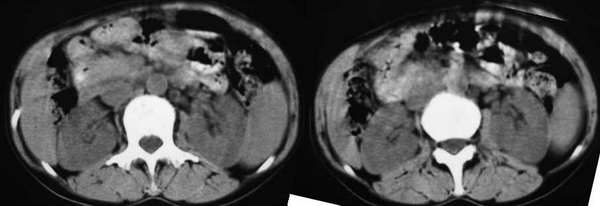

以下是引用东北在2006-1-20 15:36:00的发言:[br]图象少 外生性肝癌并肝内转移侵犯胃窦[br]胰腺的图象少

以下是引用wangqj1976在2006-1-20 21:11:00的发言:[br]不支持胰腺癌的诊断[br]1位置抬高,病变在腹腔干之上, 2胆管、胆囊主胰管不扩张,化验胆红素不高。[br]不支持肝癌[br]1无乙肝、肝硬化病史2病变强化方式[br]支持胃癌可能性大,合并肝转移、胰腺受累。(病人还贫血)[br]脾大,可以用肿瘤压迫脾静脉来解释。[br]建议做上消化道钡餐检查。